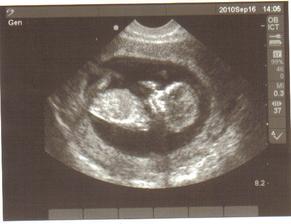

2.září: další kontrola, sestřička si zahrála na upíra a vzala mi 5 ampulek krve, dnešní UTZ parádní, prcek sebou mrskal jako o život a bude asi i fotogenickej, fotka z UTZ je úžasná, na kontrole za 14 dní už dostanu průkazku